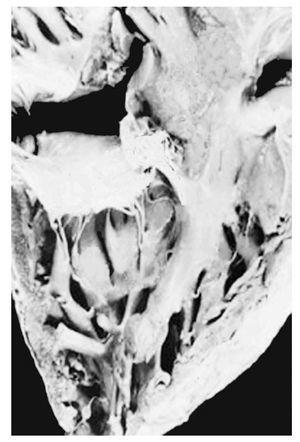

Atrio-ventricular connection: Ventricles are recognized by the trabecular septum's anatomic features. The right ventricle (Figure 3) has a trabecular septum with very thick muscular bands and it also has a structure, the moderator band, inserted in the interventricular septum and in the free wall of the right ventricle, whereas the left ventricle has a trabecular septum with very thin muscular bands in the apical section and it is smooth in the upper section (Figure 4). The former has a group of papillary muscles inserted in the free wall, and the latter has two groups of papillary muscles which are also inserted in the free ventricular wall. Trabecules provide a cavernous-type inner morphological appearance to the right ventricle, whereas the left ventricle has an areolar appearance.

Figure 4. Internal morphology of the left ventricle.